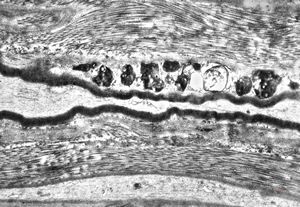

F,23y. | n.suralis - hypertrophic demyelinating neuropathy [onion bulb]

F,31y. | hypertrophic demyelinating neuropathy - n.suralis

M,13y. | n. suralis - hypertrophic demyelinating neuropathy